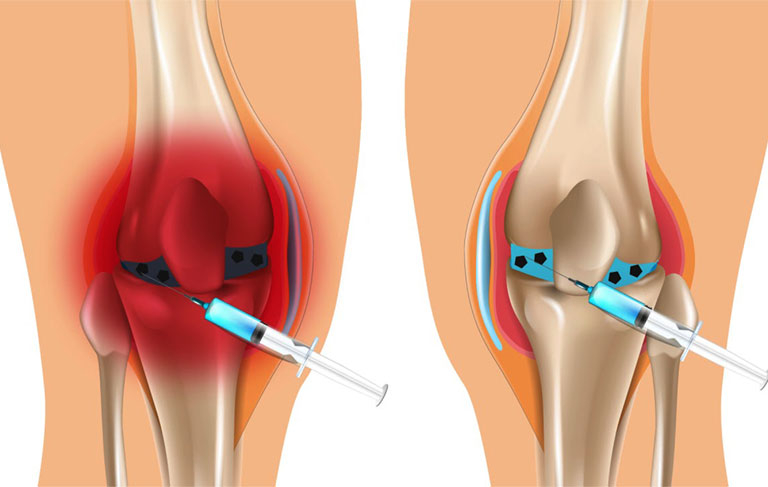

Thuốc tiêm khớp gối là phương pháp đưa trực tiếp một số hoạt chất vào bên trong khớp gối nhằm giảm đau, chống viêm và cải thiện khả năng vận động. Đây là giải pháp thường được áp dụng cho những người bị thoái hóa khớp, chấn thương khớp hoặc tình trạng đau khớp kéo dài.

Các loại thuốc tiêm phổ biến hiện nay gồm:

- Acid Hyaluronic (dịch nhờn khớp): giúp bôi trơn khớp

- Corticoid: giảm viêm nhanh

- PRP (huyết tương giàu tiểu cầu): hỗ trợ tái tạo mô

Phương pháp này thường được thực hiện tại bệnh viện hoặc cơ sở y tế chuyên khoa.